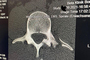

Henry Jacobi (Honda) hat bereits 3 Grands-Prix und das Motocross der Nationen mit einem gebrochenen Querfortsatz eines Rückenwirbels und unerträglichen Schmerzen absolviert. Nach eigenen Angaben geht es ihm inzwischen wieder besser. Jacobi braucht jetzt dringend gute Ergebnisse, denn bei den nächsten Rennen werden die Weichen für das nächste Jahr gestellt.